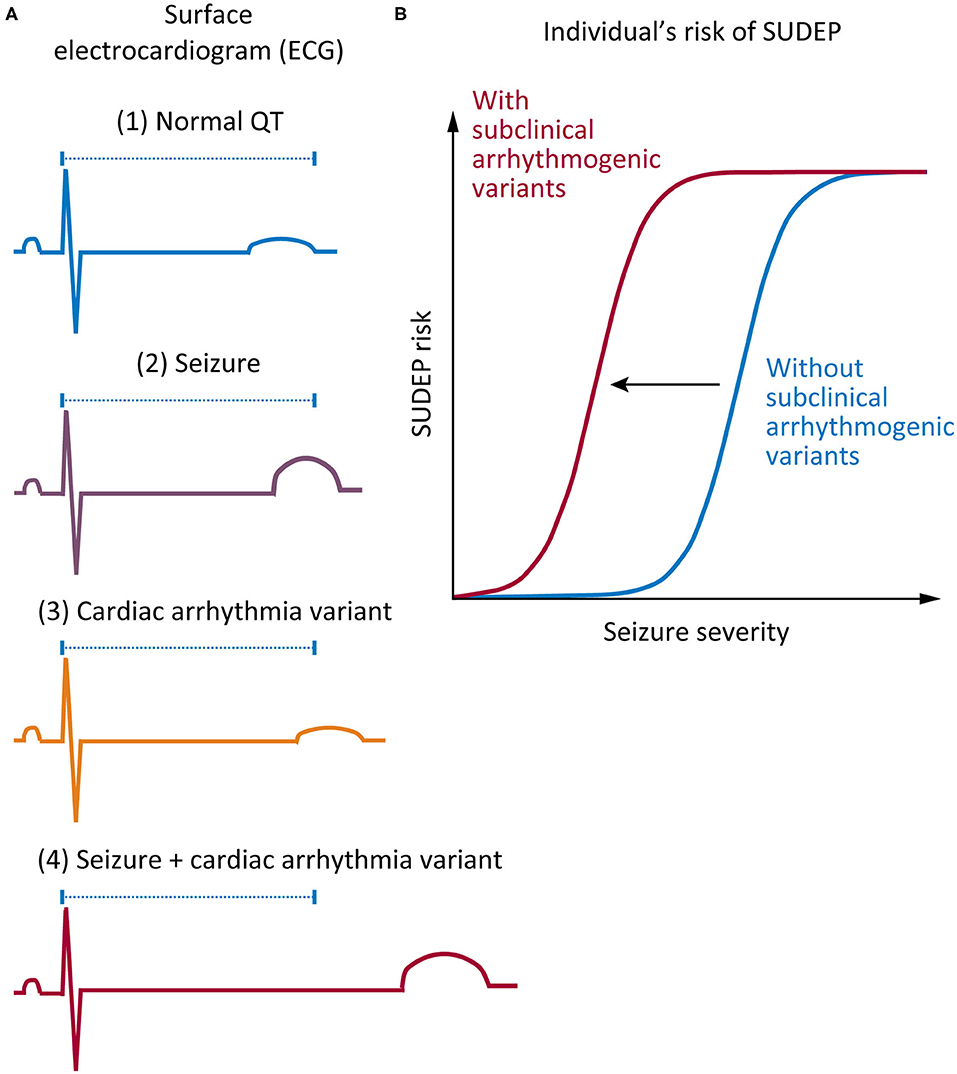

Frontiers | Are Variants Causing Cardiac Arrhythmia Risk Factors In

www.frontiersin.orgFrontiers | Are Variants Causing Cardiac Arrhythmia Risk Factors in …

www.frontiersin.orgFrontiers | Are Variants Causing Cardiac Arrhythmia Risk Factors in …